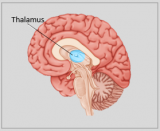

La neuroanatomie est la branche de l'anatomie qui étudie l'anatomie du système nerveux, c'est-à-dire la structure, la fonction et l'organisation du système nerveux.

Le système nerveux est l'un des systèmes les plus complexes du corps humain, et il comprend le cerveau, la moelle épinière, les nerfs périphériques et les ganglions nerveux. La neuroanatomie s'intéresse à la manière dont ces structures sont reliées les unes aux autres, comment les signaux sont transmis entre les cellules nerveuses, et comment les différentes parties du système nerveux travaillent ensemble pour contrôler les fonctions corporelles et cognitives. Les neuroanatomistes utilisent des techniques d'imagerie avancées, comme l'imagerie par résonance magnétique (IRM), la tomographie par émission de positons (TEP) et la microscopie pour visualiser les structures et les fonctions du système nerveux.